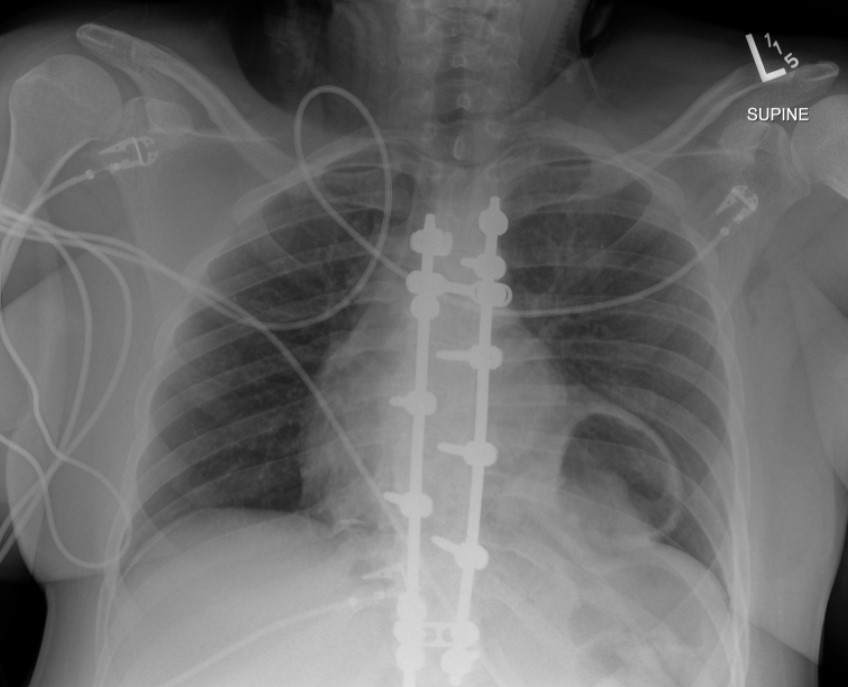

The initial chest radiograph (Figure 1) demonstrated a rounded retrocardiac partially lucent mass interpreted as a hiatal hernia.

The main radiographic finding suggesting diaphragmatic injury is the elevation of the “diaphragmatic contour” either with or without visualization of a herniating hollow viscus. This may be difficult to differentiate from preexisting hiatal hernia, basilar atelectasis, diaphragmatic eventration, congenital hernias, and phrenic nerve injury which may have a similar appearance. Furthermore, as with our case, positive pressure ventilation may lead to delayed diagnosis due to temporary reduction of the intraabdominal contents. The reported rate of missed diaphragmatic injury on chest radiographs is variable and ranges from 12 to 66%. CT has higher sensitivity and specificity for the diagnosis of diaphragmatic injuries. CT findings include visualization of the discontinuity of the diaphragm (73% sensitivity, 90% specificity), intrathoracic herniation of viscera (55% sensitivity,100% specificity), the collar sign (63% sensitivity, 100% specificity), which refers to a waist like constriction of the herniated viscera where it extends through the diaphragmatic defect, and the dependent viscera sign (90% sensitivity, 100% specificity) which describes the positioning of the abdominal viscera directly anterior to the posterior ribs due to loss of the diaphragmatic structural support.

- Radiographic diagnosis of blunt left diaphragmatic injury may be suggested by elevation of the “diaphragmatic contour,” which can be misinterpreted as the result of other abnormalities.

- Positive pressure ventilation can reduce the herniated viscera into the abdominal cavity and conceal the radiographic findings of a diaphragmatic injury.